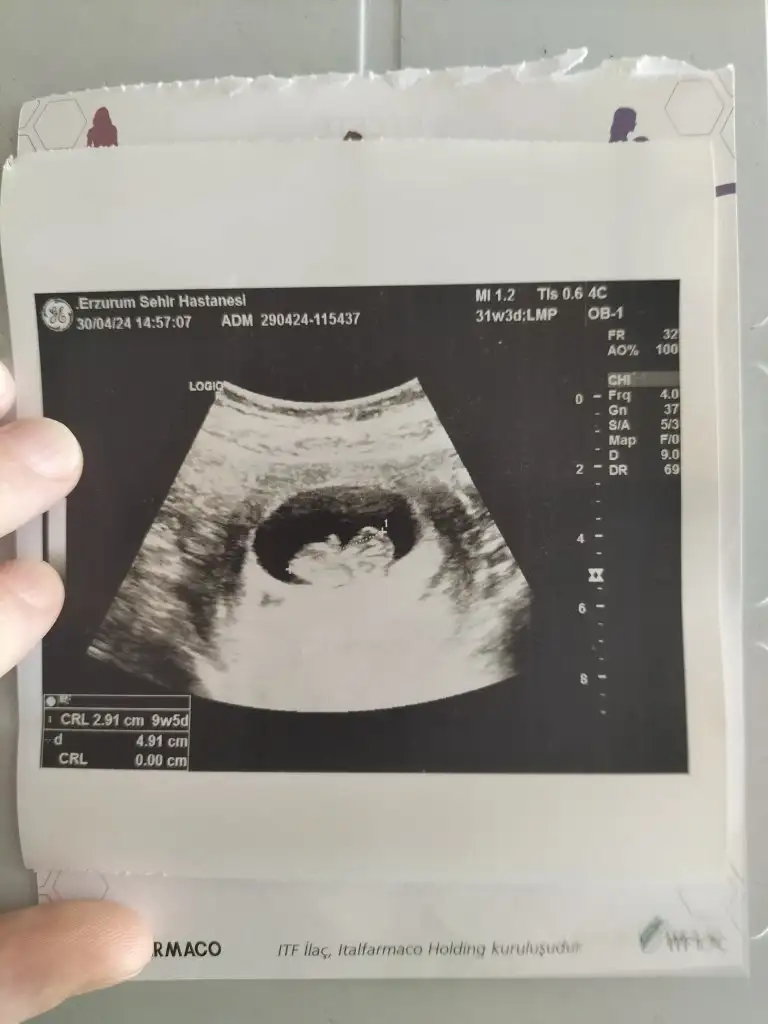

Merhaba 12+2 haftalık rica etsem banada cinsiyet tahmini yapabilir misiniz sırasıyla 5 hafta 7 hafta ve 12+2 haftalık

Kız gıbı cnm nup düz geldı bana hayırlısıyla saglıklı gelsın dünyaya kuzun